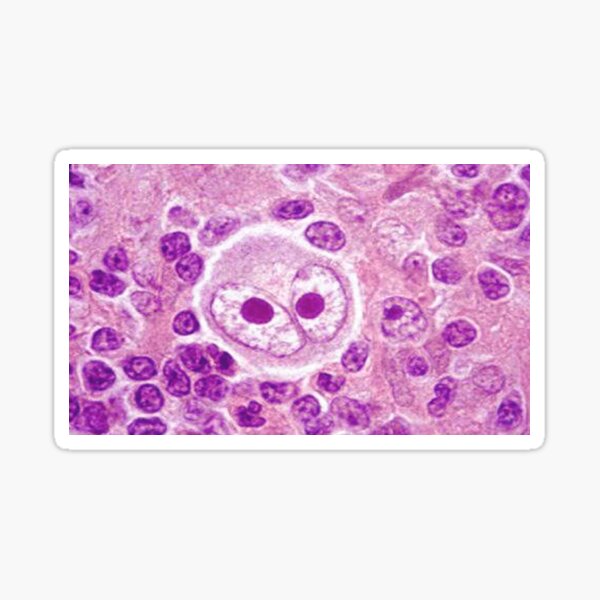

Микропрепараты: Лимфогранулематоз и Нодулярный Склероз

Раздел: Секреты мастерства